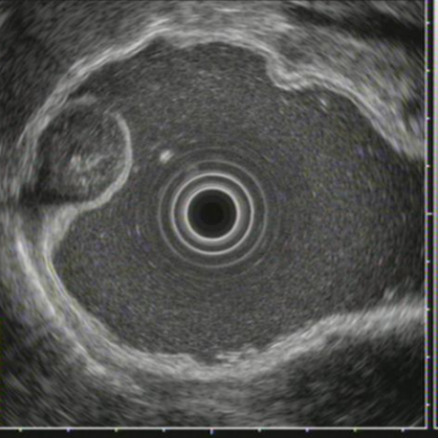

⑦超声胃镜

EUS是将微型高频超声探头安置在内镜前端,在内镜直视观察腔内形态的同时,又可进行实时超声扫描近距离探查,使靶器官的结构与图像更为清楚,为临床治疗方案的选择提供了有力的支持。我院消化内镜于2004年在四川省率先开展EUS新技术,目前拥有国内最新—代的EUS系统,它集超声内镜主机、高频小探头、三维超声探头、环扫内镜超声等 先进设备为—体。我院EUS诊疗组,现有教授1名、副教授2名,每年完成近千例消化道EUS诊疗,EUS诊疗技术达到省内先进水平。

为什么需要EUS

普通内镜检查只能发现消化道表面的病灶,通过EUS显示消化管壁层次结构及周围脏器病变,能更准确判断胃肠隆起病变的 性质、来源、肿瘤的浸润深度,还能取活检,指导确定治疗方案及判断疗效。